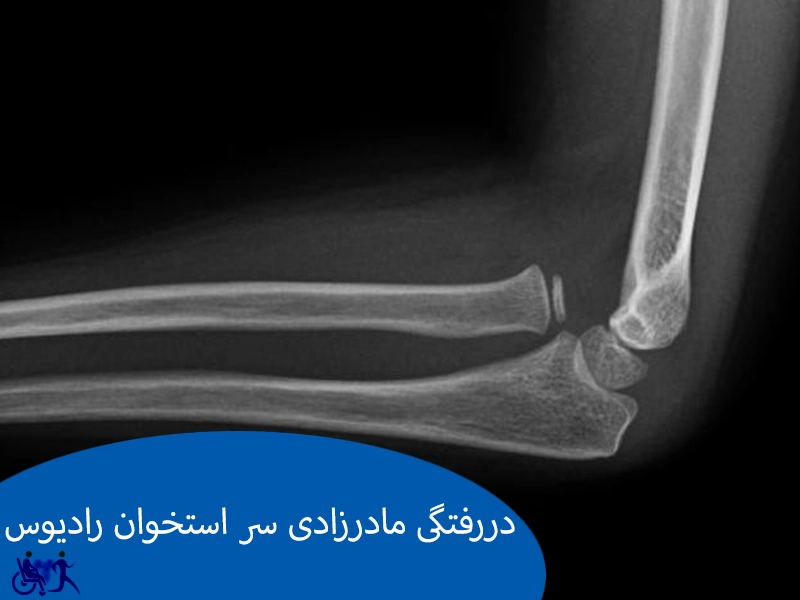

دررفتگی مادرزادی سر استخوان رادیوس یک ناهنجاری نسبتاً نادر در ناحیه آرنج است که طی آن سر استخوان تحتانی بازو (رادیوس) از جای طبیعی خود خارج میشود و بهطور صحیح در مفصل آرنج قرار نمیگیرد. این مشکل معمولاً از بدو تولد وجود دارد و برخلاف دررفتگیهای ناشی از ضربه، درد شدیدی ایجاد نمیکند؛ به همین دلیل ممکن است تا سنین بالاتر تشخیص داده نشود. والدین معمولاً زمانی متوجه مشکل میشوند که کودک هنگام چرخاندن ساعد یا خمکردن آرنج محدودیت حرکت دارد یا شکل آرنج کمی غیرعادی به نظر میرسد.

این عارضه میتواند بهتنهایی رخ دهد یا همراه با مشکلات مادرزادی دیگر مثل اختلالات رشد استخوانی باشد. درمان بسته به شدت جابجایی و میزان محدودیت حرکتی متفاوت است. در موارد خفیف معمولاً درمان خاصی لازم نیست و فقط فیزیوتراپی برای بهبود حرکت پیشنهاد میشود. اما اگر دررفتگی باعث ناتوانی حرکتی یا درد شود، جراحی گزینهای برای اصلاح جای مفصل و بهبود عملکرد آرنج خواهد بود.